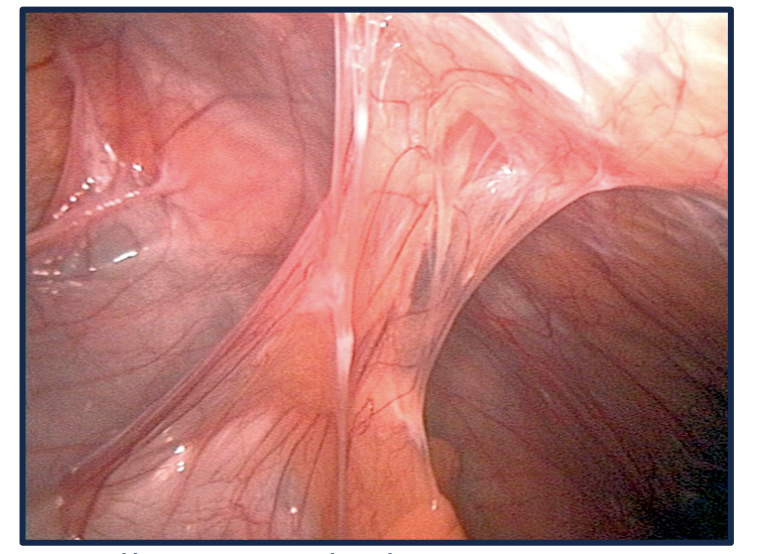

* Adhesions are fibrous bands outside the bowel that cause the bowel to be tethered